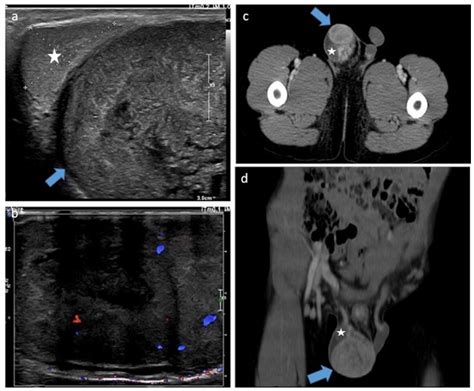

Diagnosing a testicular cyst typically involves a combination of the following:

• Physical Examination: A healthcare provider will perform a physical exam to feel for any lumps or abnormalities.

• Ultrasound: An ultrasound of the scrotum can help visualize the cyst and determine its size and location.

Diagnosis

Diagnosing testicular cancer involves several steps:

• Ultrasound: An ultrasound of the scrotum can help visualize the tumor and determine its size and location.